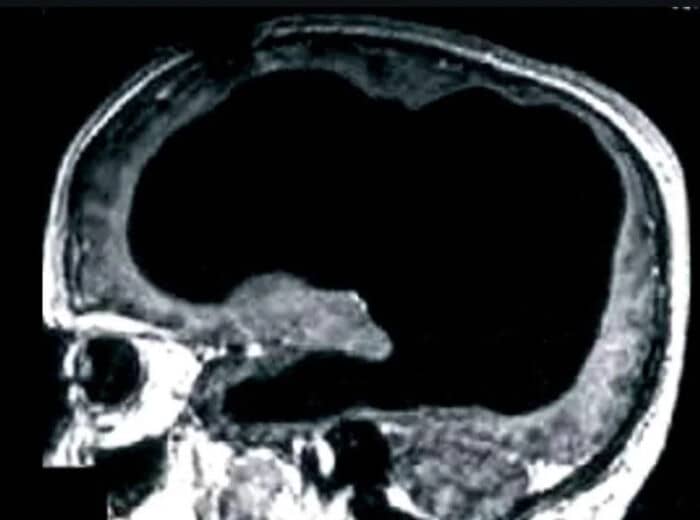

#20 A Man Was Discovered To Be Unknowingly Missing 90% Of His Brain, Yet He Was Living A Normal Life

#92 Redditors Are Literally Missing Parts Of Their Brains